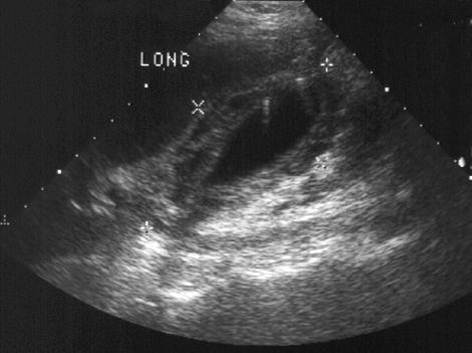

Adenomyomatosis

(Thickened gallbladder wall with comet tail artifact)